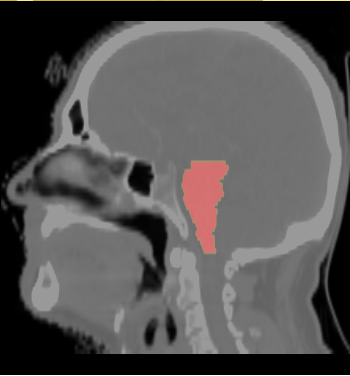

- We selected the ROI of every data excluding lung and chest. For each data there exist the segmentations of brain stem, left and right parotids. For example

- We constructed the average atlas of 20 datasets of ROI, and merged the segmentations into the average atlas. These segmentations are the probability maps of

brain stem, left and right parotids.